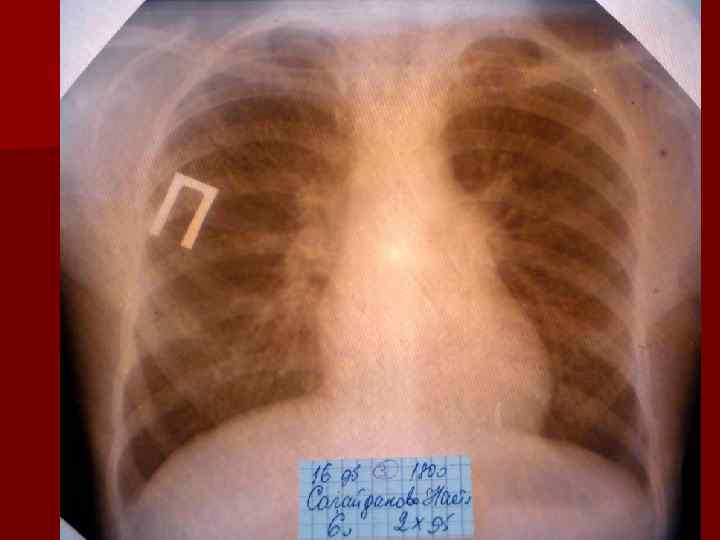

Долевая пневмония характеризуется лобарным пневмоническим инфильтратом. Крупозная ( пневмококковая) пневмония диагностируется прежде всего по клиническим данным. Крупозная пневмония сохраняет свою типичную картину пневмококковой пневмонии: острое начало с характерными клиническими данными, циклическое течение, несклонность к деструкции, гомогенной и лобарной инфильтративной тенью при рентгенологическом исследовании. Вместе с тем, широкое использование антибиотиков способствовало значительному снижению числа крупозных пневмоний у детей. Интерстициальная – редкая форма пневмоний, при которой оказывается поражен прежде всего интерстиций. Как правило, интерстициальная пневмония обусловлена вирусами, пневмоцистами, внутриклеточными микроорганизмами и грибами.

Морфологическую форму пневмонии определяют по клинико – рентгенологическим данным: выделяют очаговую, очагово – сливную, долевую ( крупозную), сегментарную и интерстициальную пневмонии. Очаговая – наиболее распространенная форма. Пневмонические очаги чаще бывают размером 1 см и более. Очагово – сливная – инфильтративные изменения в нескольких сегментах или во всей доле легкого, на фоне которых могут быть видны более плотные участки инфильтрации и/или полости деструкции. Сегментарная – в процесс вовлекается весь сегмент, который, как правило, находится в состоянии гиповентиляции, ателектаза. Морфологическая картина воспаления при очаговых и сегментарных пневмониях связана с первичным инфекционным воспалением в бронхах, что дает основание отнести эти варианты поражения легочной ткани к бронхопневмониям, нередко сопровождающихся бронхообструктивным или бронхообтурационным синдромами. В настоящее время данный тип пневмоний у детей встречается наиболее часто.